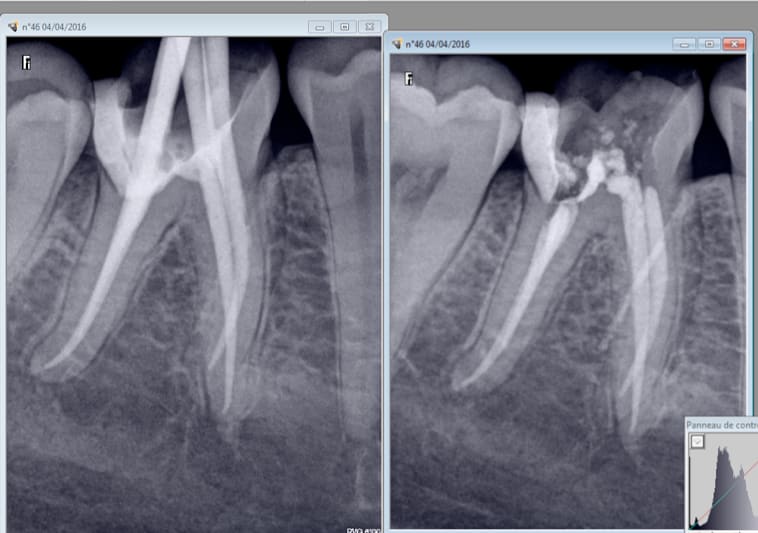

Oui l'année dernière. je me demandais si c'était pas l'aiguille du quick sleeper qui avait traversé la racine. -)

Avant thermocompaction et après thermocompaction. Et merde. -)

Mais bon RAS 10 mois après. Si ce n'est qu'elle a perdu de la durée devie car c'était un peu ramollo au niveau du canal distal. J'aurais bien fait le pivot dans un des mésiaux mais j'ai pas osé. -)))